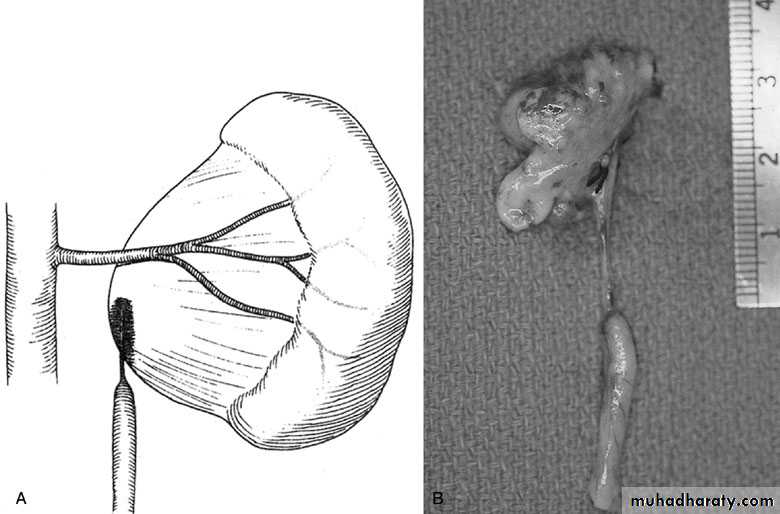

Open & laparoscopic surgical techniques Anderson-Hynes dismembered pyeloplasty: excision of the pathologic UPJ & appropriate reanastamosis or flap technique or flap operation

SURGICAL REPAIR including open surgical techniques, laparoscopic, & endoscopic approaches

Nephrectomy for non functioning kidney